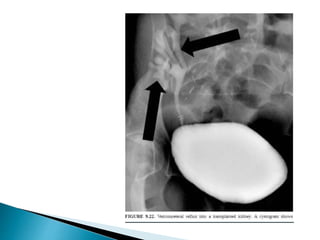

 Heterotopic renal transplantation.

1. Donor kidney is placed in an extra peritoneal location in

iliac fossa.

2. Renal artery and vein is anastomosed to external iliac

vessels

3. Urinary tract is reconstructed by an anti-refluxing

urterneocystostomy.